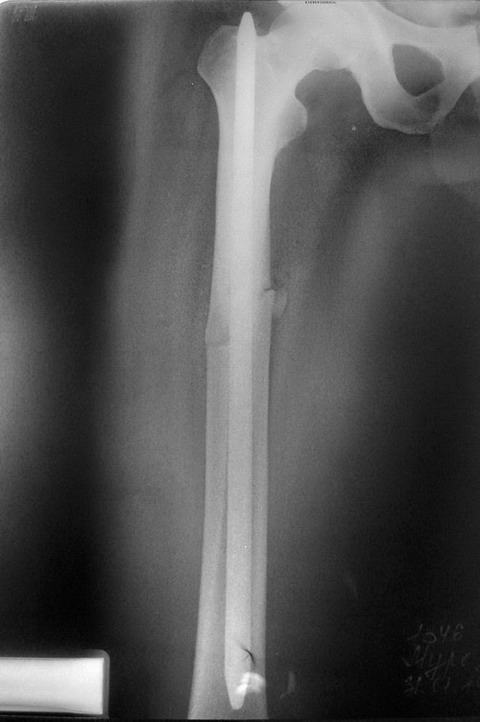

[Ortho] Повторный перелом бедра

Что, неужели у вас не нашлось хотя бы такого архаического стержня для

жителя глубинки?